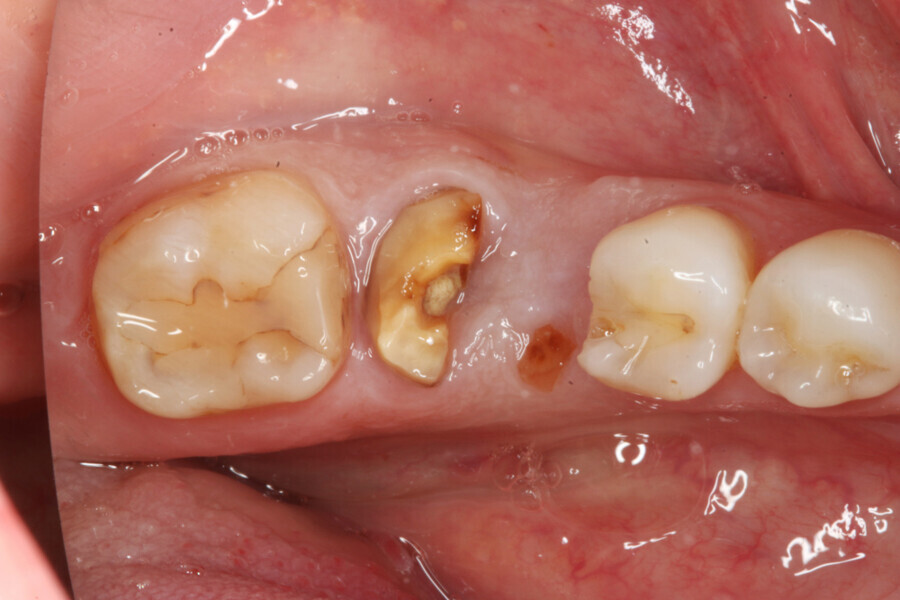

A 39-year-old male patient presented with a deeply fractured mandibular first molar two years after hemisection (Fig. 1). After the patient had opted for an implant-borne solution, an immediate implant placement and restoration with a PMMA provisional crown on a final Atlantis abutment (Dentsply Sirona) was planned.